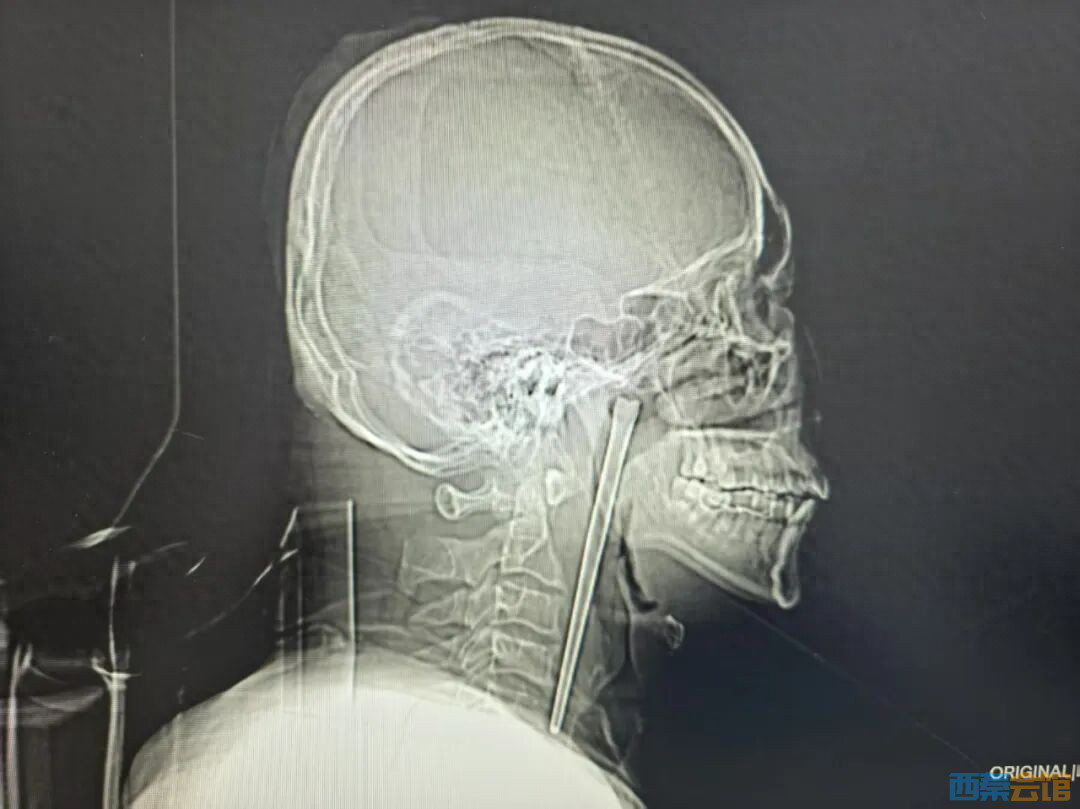

近日,大连理工大学附属中心医院耳鼻咽喉头颈外科收治了一名特殊患者。今年46岁的王先生因咽部突发剧烈疼痛、异物感强烈而紧急就医,影像检查的结果让医护人员都感到意外——一根长达12厘米的金属筷子,竟然已经在他咽部“滞留”了整整八年。

据了解,八年前,王先生在吃饭时不慎将整根金属筷子误吞入喉。当时他立刻感到颈部有强烈的哽咽感和疼痛,所幸并未出现呼吸困难。虽然第一时间前往当地医院就诊,但在得知需要通过颈部切开手术才能取出异物后,王先生因担心手术创伤而选择放弃治疗,这根筷子便留在了咽部。

经详细检查发现,一根金属筷子嵌顿于王先生右侧咽后壁上方、软腭后侧,体外可见部分长约3厘米。值得庆幸的是,筷子周围的咽部黏膜并未出现明显破损、出血或化脓,声带活动及喉腔结构也未受压迫。

考虑到患者曾因顾虑传统颈部切开手术而放弃治疗,耳鼻咽喉头颈外科团队为他量身定制了经口腔入路的微创手术方案。手术无需在颈部切口,最终顺利将整根长达12厘米的不锈钢筷子完整取出。术中出血极少,未出现任何并发症,患者术后恢复良好,终于摆脱了长达八年的“心头之患”。